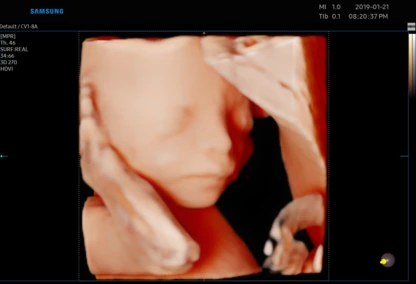

USG 3D dziecka w poradni ginekologicznej w Zambrowie –ocena NT, PAPP -A

Każdą kobietę w ciąży otaczamy kompleksową opieką, czuwając nad jej zdrowiem oraz prawidłowym rozwojem płodu. Podczas regularnych wizyt, zlecamy odpowiednie badania laboratoryjne. Korzystając z najnowszej generacji aparatu USG, przeprowadzamy bardzo dokładną diagnostykę obrazową – łącznie z USG 3D/4D płodu.

• Najnowsza generacja aparatu USG pozwala na przeprowadzanie dokładnej diagnostyki obrazowej, diagnostyki przepływów (Doppler).